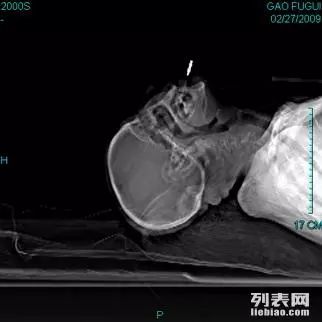

看图说话,标准化程序如下:患者仰卧位,肩下垫枕,头尽量后仰使鼻尖和 外耳道连线垂直于地面,调整C型臂,从下颌向头顶投照,显示颅底黄豆大小的卵圆孔,然后把一根长10厘米的穿刺针从口角穿刺经卵圆孔进入颅内到达半月神经节,在神经刺激器的引导下将电极调整到三叉神经三个分支中的一个,测试无误才能开始手术。

这个病人从颈椎直到到膝关节,整个脊柱形成了一个大写字母C,平卧,不可能,头后仰30度??开玩笑,病人头前屈20度且完全强直固定.....角度差了50度呢......要不把这个难题推走?这个明显不是我的风格吧,老太太期盼的眼神看着我呢!进修生崇拜的眼神看着我呢!何况还有灰常好看的志愿者妹妹站在旁边呢.......